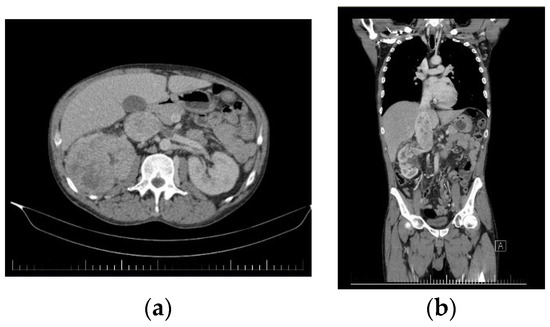

2. Case Report